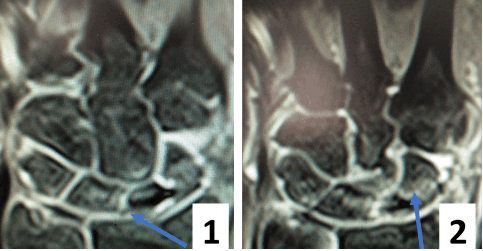

(Слева) МР-артрография в режиме Т1ВИ FS, коронарный срез: определяется разрыв тыльной части ЛПС. Контрастный препарат через дефект распространяется в среднезапястный сустав. Также отмечается разрыв треугольного фиброзно-хрящевого комплекса (ТФХК), вследствие ко торого контрастный препарат поступает в дистальный лучелоктевой сустав.

(Справа) МР-артрография в режиме Т1ВИ FS, коронарный срез, этот же пациент: определяются разрывы мембранозной части ЛПС и мембранозной части треугольного фиброзно-хрящевого диска. (Слева) МР-артрография в режиме Т1ВИ FS, аксиальный срез: визуализируется интактный тыльный пучок, ладонный пучок поврежден. Следует отметить расширение суставной щели, истончение хряща и кисто-зоподобную перестройку.